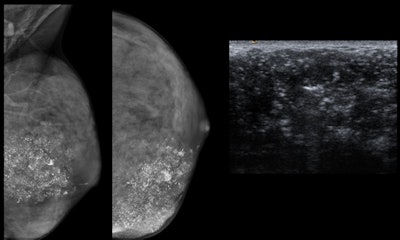

- Mammograms should be performed only in patients with lesions not completely clarified by ultrasound as a complementary technique depending on initial findings and the degree of suspicion.

- In children, when necessary, the initially recommended imaging technique is breast ultrasound.